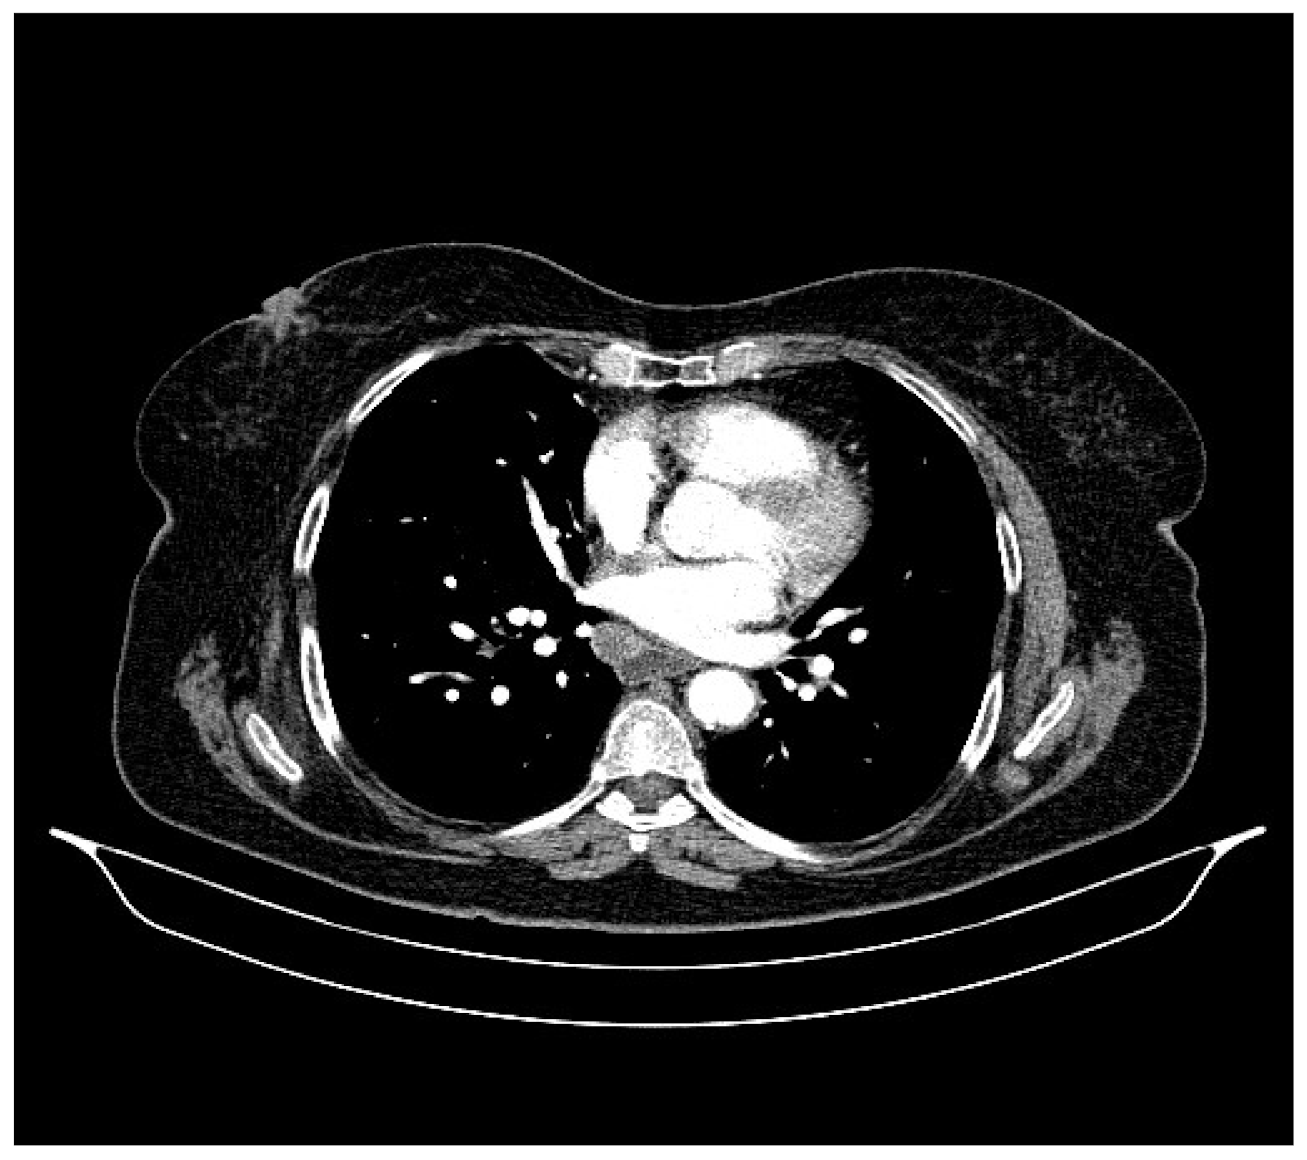

2. Case Presentation